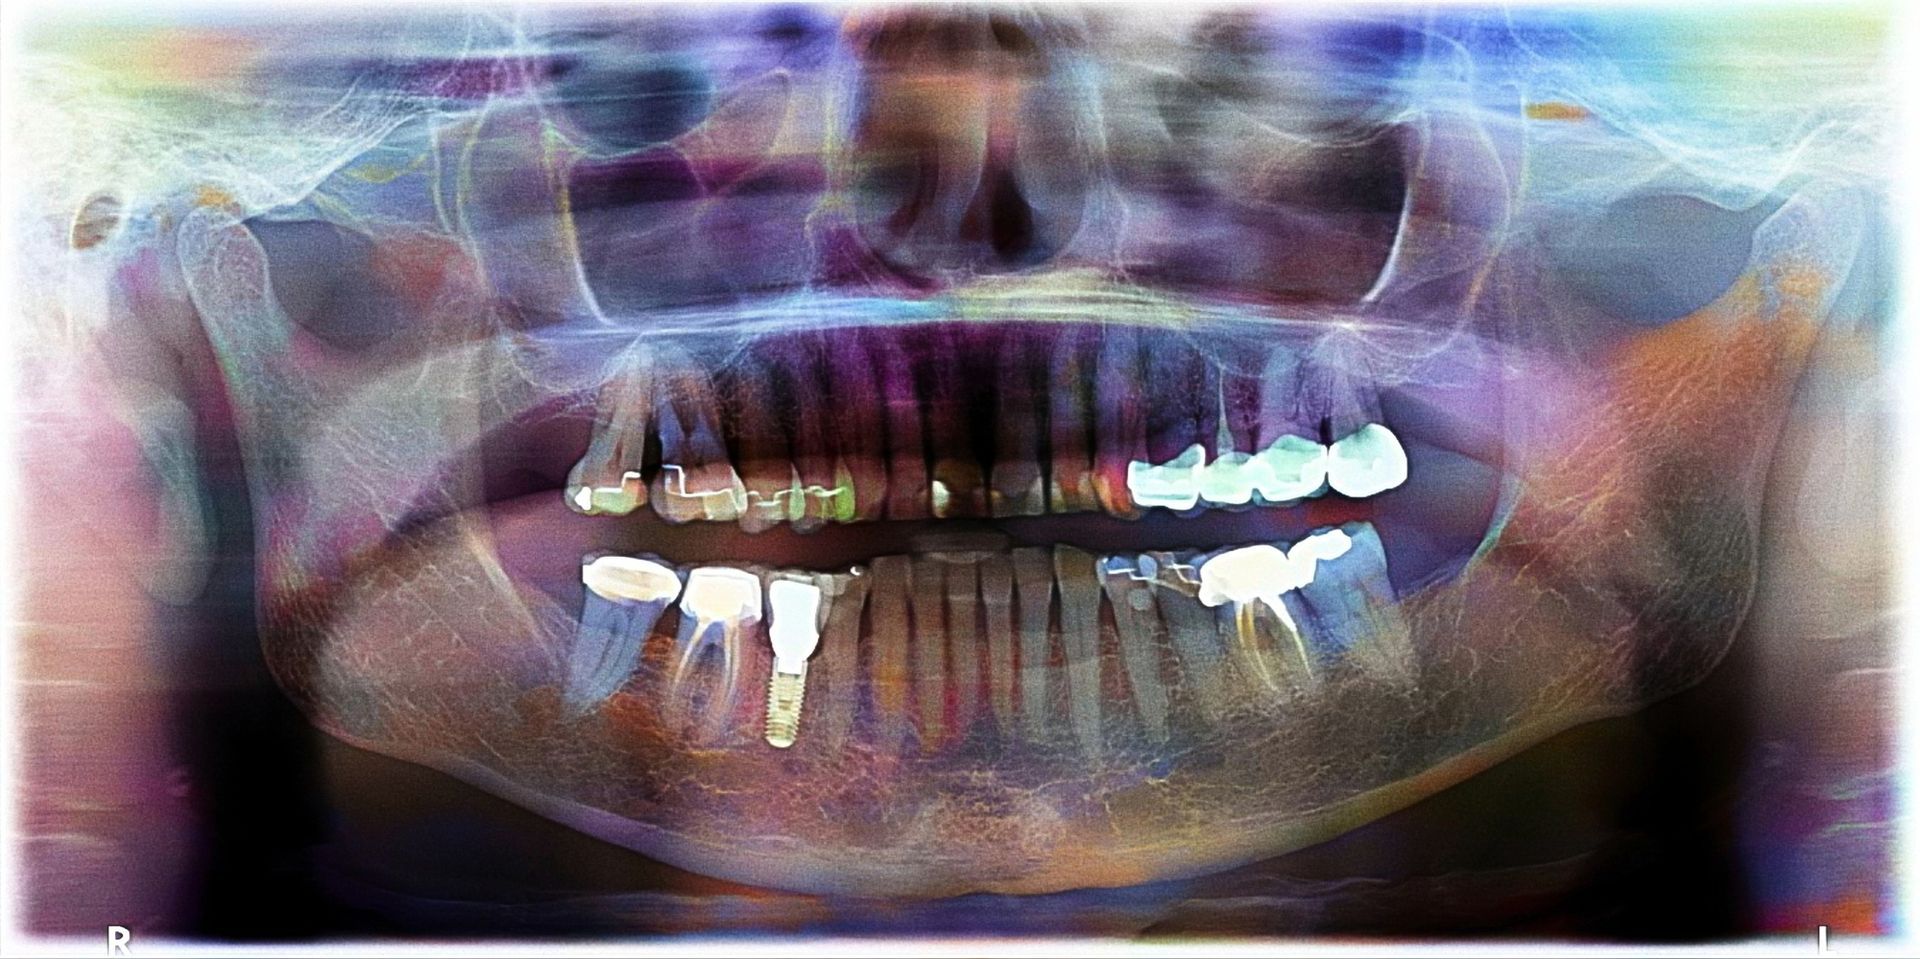

Panoramica dentale: caratteristiche e utilizzi clinici

La panoramica dentale, o ortopantomografia, è un esame che consente la visualizzazione simultanea dei denti, delle articolazioni e delle strutture ossee di mascella e mandibola. Le immagini ottenute permettono di valutare la presenza di carie non immediatamente riconoscibili, di controllare lo stato della dentizione, di individuare denti inclusi o non erotti e di analizzare la quantità e la qualità dell’osso qualora si renda necessario un trattamento implantologico. La lettura accurata dell’immagine può mettere in evidenza lesioni come granulomi, cisti o alterazioni dell’osso che richiedono approfondimenti mirati.

L’esame viene di norma eseguito in posizione eretta, ma può essere svolto anche seduti quando necessario, purché venga mantenuta un’adeguata immobilità per evitare artefatti. La

Panoramica Dentale e Telecranio a Casarano (LE) si affida a sistemi digitali che riducono il dosaggio radiogeno e assicurano una resa molto definita, rendendo questo accertamento un elemento essenziale nella fase preliminare di qualsiasi trattamento odontoiatrico. Prima dell’esame è indispensabile rimuovere tutti gli oggetti metallici presenti nell’area del capo, così da evitare interferenze con i raggi X e ottenere una visualizzazione corretta delle strutture da esaminare.